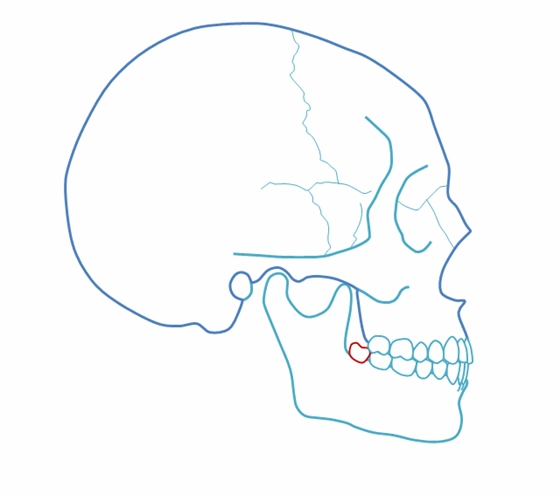

完全埋在牙槽骨里的下頜智齒,它本身倒是不出問(wèn)題。但是這些近中或水平阻生的智齒,會(huì)推擠下頜第二磨牙,導(dǎo)致第二磨牙伸長(zhǎng):

然后,第二磨牙造成咬合干擾、早接觸,前牙開(kāi) 牙合…………

甚至髁突吸收:

所以,這種智齒也還是要拔掉。